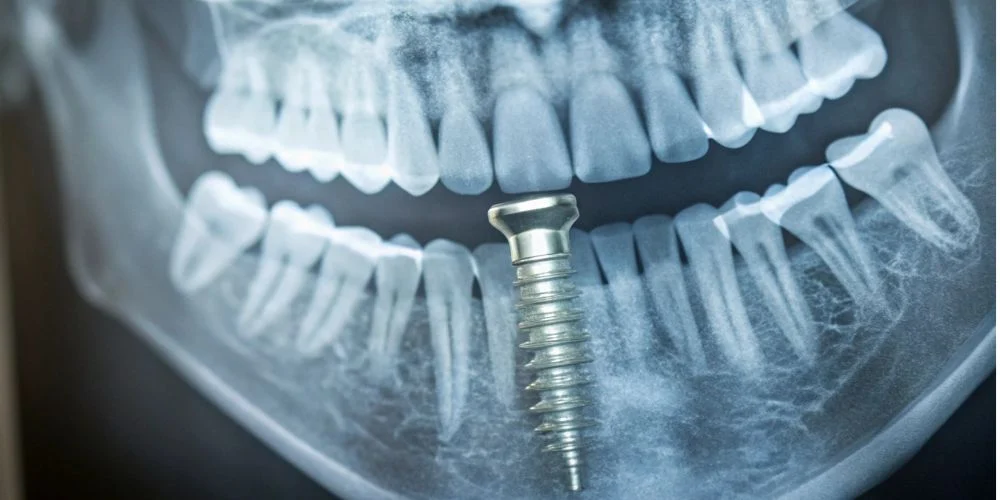

Dental implant failure occurs when your implant becomes loose, falls out, or cannot support your replacement tooth. The timing of failure helps determine the cause, with early failures happening during healing and late failures occurring years later.

Your implant may fail if it never properly fuses with your jawbone. This process is called osseointegration, where your bone grows around the implant to hold it in place.

When osseointegration fails, your implant cannot create a stable foundation. Your body may also reject the implant or develop an infection around it.

Osseointegration is when your jawbone grows around and fuses with your implant. This process usually takes 3-6 months and creates a strong foundation for your new tooth.

X-rays and CT scans reveal bone loss around the implant that you can’t see or feel. These images show the bone level and density surrounding your implant.